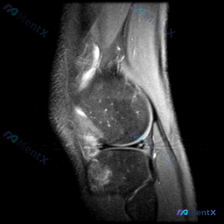

今天整理了一例膝关节单张MRI矢状位T2加权像的读片分析,核心问题一开始指向半月板异常,但实际读下来发现核心问题不在这,分享一下思路,大家一起讨论。

这是单张膝关节MRI矢状位T2加权图像,影像所见如下:

- 骨骼骨髓信号:胫骨近端前部(前胫骨平台下方)可见边界模糊的明显高信号影,符合骨髓水肿表现;股骨远端骨髓信号无异常,骨皮质轮廓基本正常。

- 半月板:可见的半月板体部信号大致均匀,没有看到延伸到关节面的撕裂性高信号影。

- 交叉韧带:前交叉韧带走行可见,但近端附着点附近及前方存在高信号影,考虑水肿或软组织肿胀,需要结合其他序列判断连续性。

- 关节腔与软组织:关节腔内可见少量高信号液体影,提示轻度关节积液;髌下脂肪垫信号增高,轮廓稍模糊,提示局部炎性改变或水肿;髌腱及周围软组织没有看到明确断裂,但前方软组织也有局部信号增高。